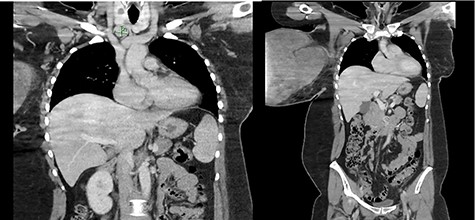

Enlarged supraclavicular lymph node and partially imaged massive tumour in the right breast.

The wound swab showed heavy growth of Staphylococcus aureus susceptible to Flucloxacillin. On ultrasonography, the right breast was completely replaced by a massive solid, heterogenous mass. It demonstrated internal vascularity and numerous cleft cystic spaces and leaf-like internal architect. Mammogram was not feasible due to the incompressible nature of the right breast, patient discomfort and the size of the lesion. A chest computed tomography was ordered for staging/metastatic workup and preoperative planning. Multiple enlarged right axillary lymph nodes measuring up to 12 mm and a 19 mm lymph node in the right supraclavicular region were noted with no distant metastasis (Fig. 2). The core biopsy showed features of spindle cell lesion with the differentials being borderline PT versus metaplastic carcinoma.